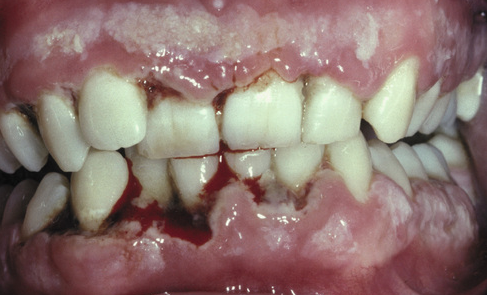

What is the likely diagnosis?

Necotizing ulcerative gingivitis.